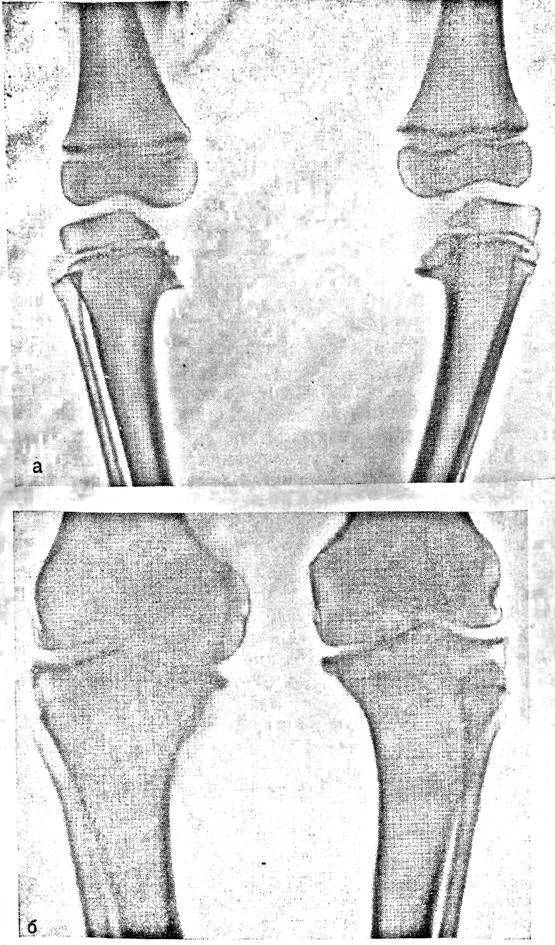

Аппарат Илизарова: принцип работы и применение